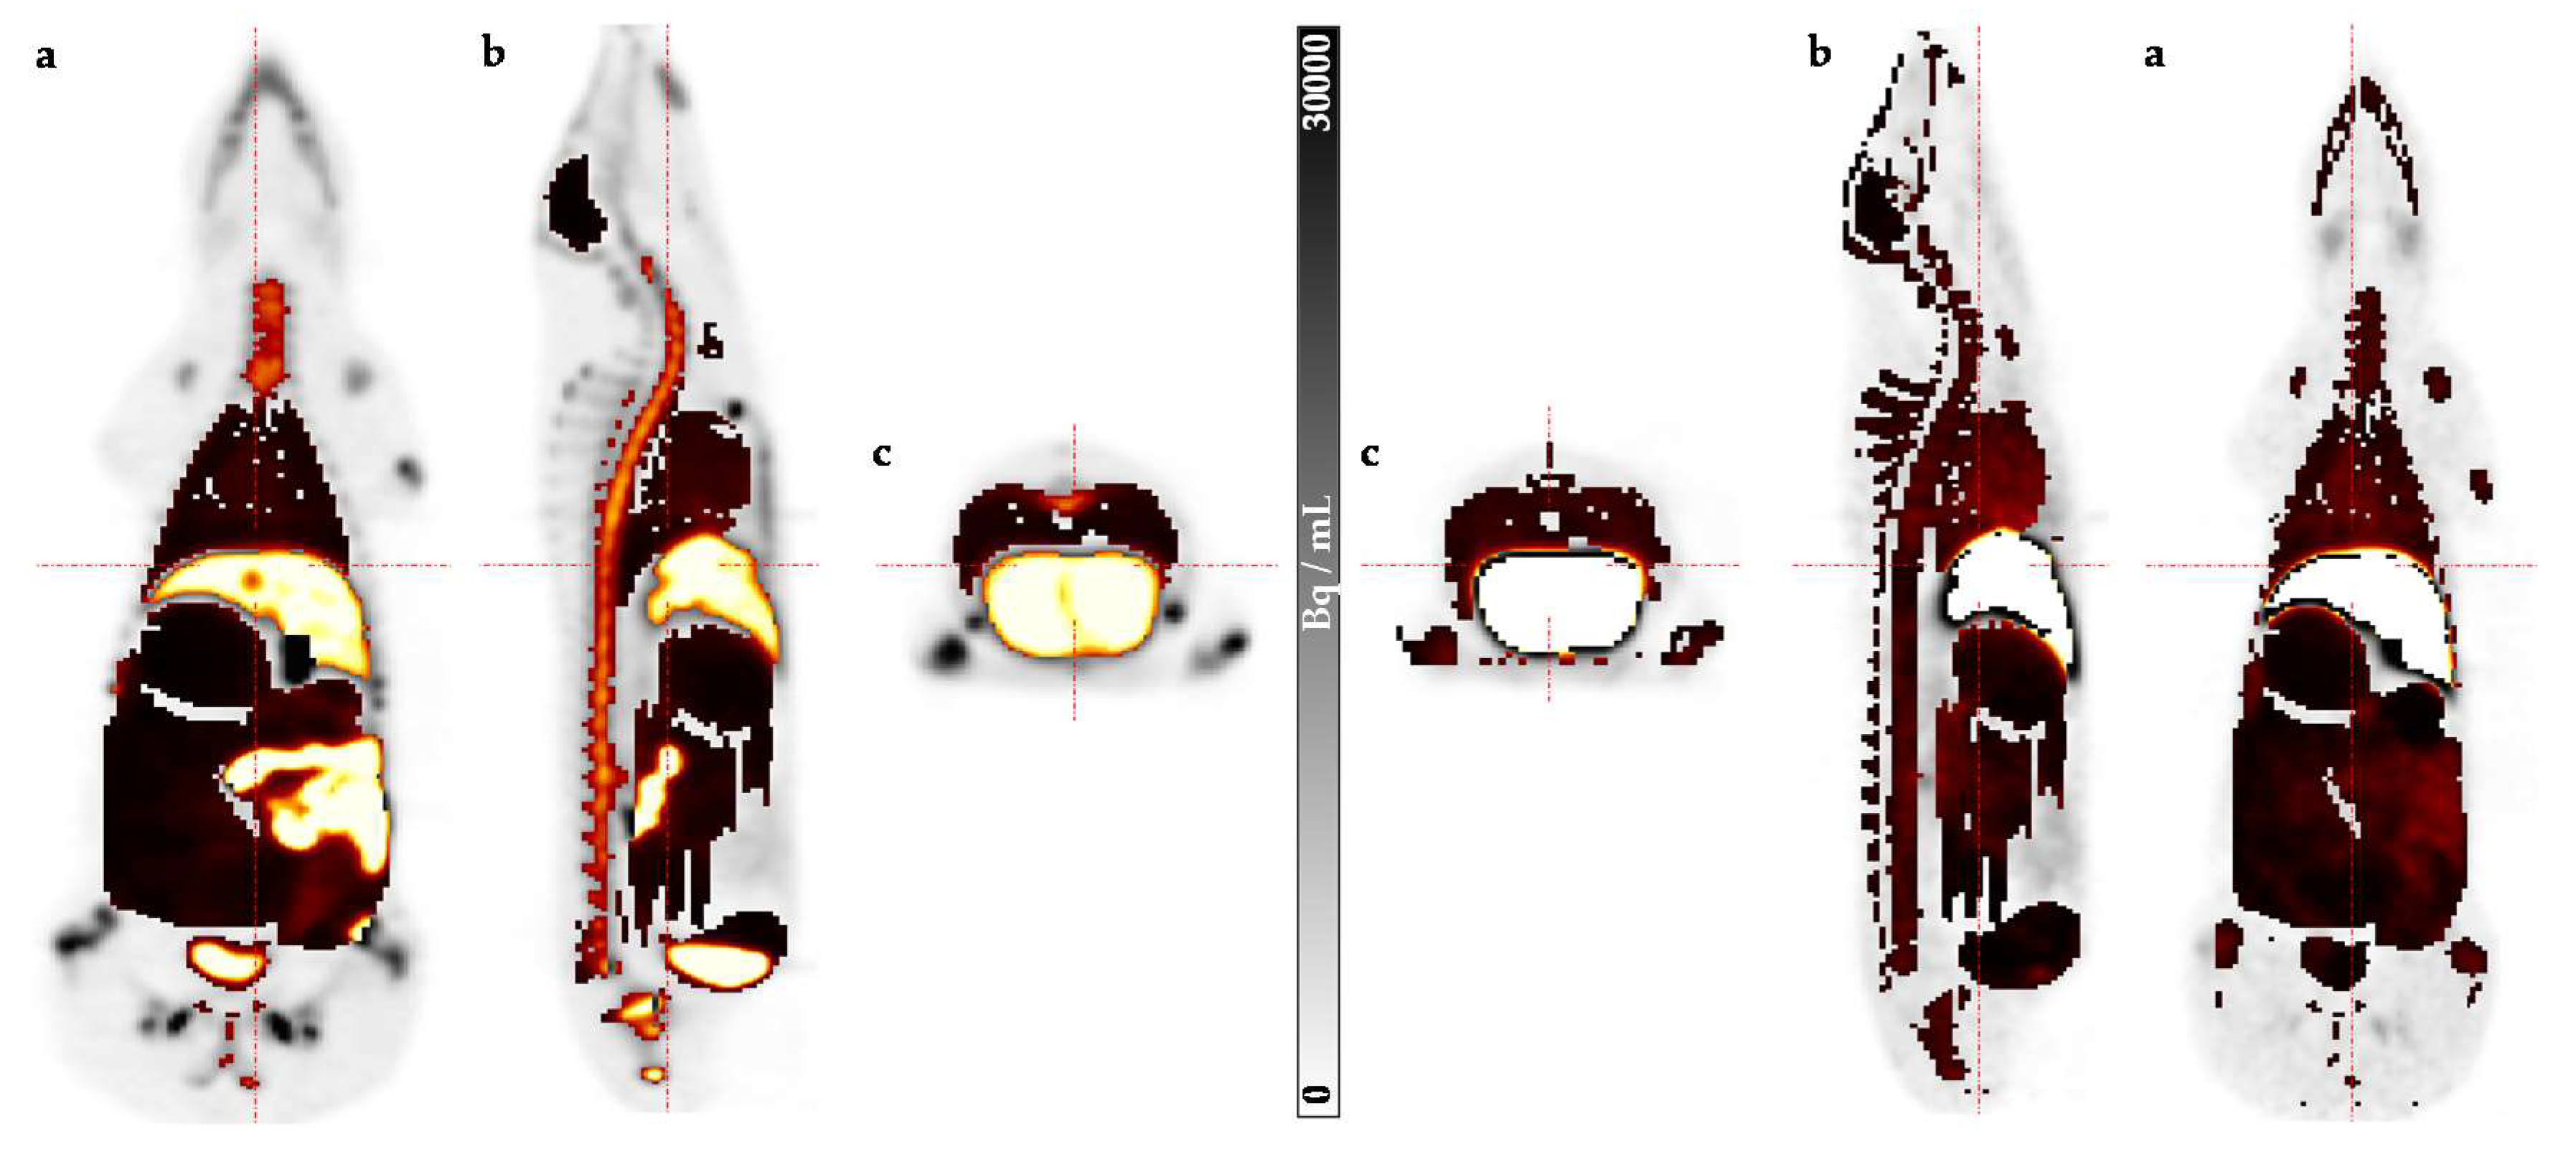

2. Results

3. Discussion

4.2. Preclinical Dosimetry Studies—In Vivo PET/CT Imaging in Pigs

4.3. Image Analysis